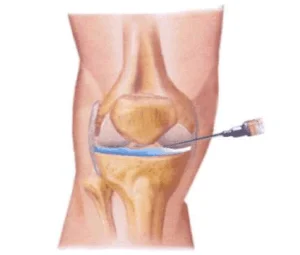

Knee Arthroscopy

Your doctor may recommend knee arthroscopy if you have a painful condition that does not respond to nonsurgical treatments as listed above. Knee arthroscopy may relieve painful symptoms of many problems that damage the cartilage surfaces and other soft tissues surrounding the joint.